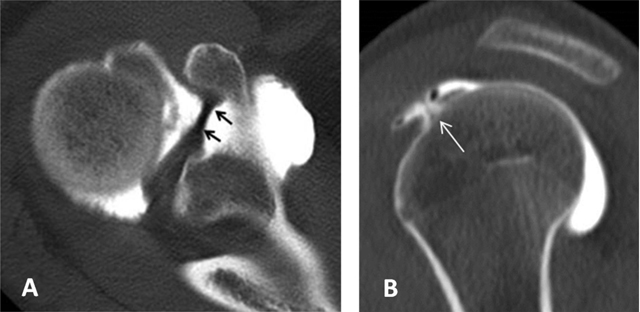

Figure 17

Superior glenohumeral ligament. It can be seen as a medium-size structure running almost straight from the superior labrum into the direction of the coracoid process on axial CTA (black arrows, (A). On sagittal CTA, the ligament appears as a T-shaped structure (thin white arrow, (B) Interposed between the long head of the biceps tendon posteriorly and the subscapularis tendon anteriorly.